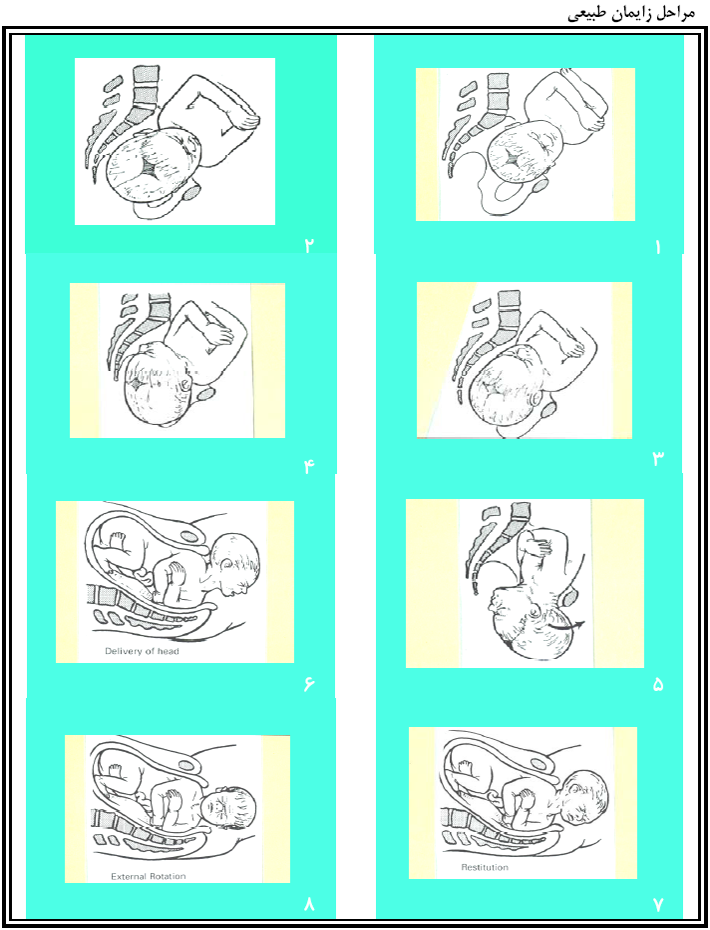

قیمت: 29٬000 تومان - دسته بندی فایل: علوم پزشکیزايمان، وضع حمل و نفاس

زايمان، وضع حمل و نفاس